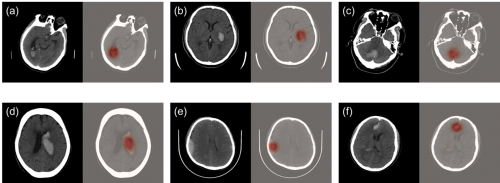

科亞醫療的“CuraRad-ICH是一款專注于對腦卒中進行快速腦部出血預警的AI影像分析處理軟件,可以通過深度學習技術準確、快速地篩查急性腦出血病例,并直接無縫接入醫院PACS系統, 自動升高腦出血病例的優先級,提示影像科醫生優先完成病患的診斷評估,從而有效縮短腦卒中病患的診斷治療時間,挽救生命。

在來自全美48個州296家影像中心的臨床測試中,CuraRad- ICH分析處理軟件達到了91%的敏感性和93%的特異性,同時平均每次預警僅耗時43秒,大幅度縮短出血性腦卒中病患的診療時間,受到臨床專家的一致認可。